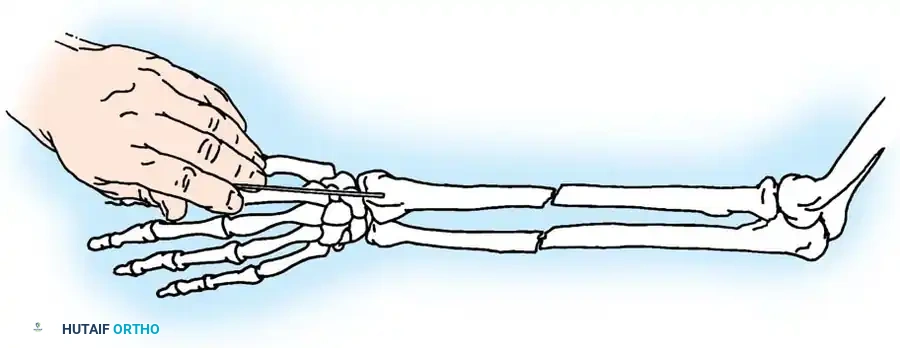

Fig. 54-53 A and B, Simple loop is not as satisfactory as figure-of-eight loop for fixing fracture of olecranon. C, Simple loop is insufficient when its long axis is in or anterior to long axis of olecranon.

🔪 Surgical Technique: Tension Band Wiring

- Exposure: Expose the fracture site and clear the joint of hematoma and small osteochondral debris.

- Drill Hole: Drill a transverse hole from side to side in the distal ulnar fragment, approximately 2 to 3 cm distal to the fracture line. Ensure the hole is deep enough to avoid cutting through the posterior cortex.

- Wire Passage: Pass an 18-gauge (1.2 mm) stainless steel wire through the drill hole.

- Proximal Purchase: Pass the wire beneath the aponeurosis of the triceps muscle, directly adjacent to the bone, and around the tip of the olecranon. Alternatively, a transverse drill hole can be made in the proximal fragment if it is large enough.

- Figure-of-Eight: Carry one end of the wire obliquely across the posterior aspect of the fracture to the opposite side. Cross the other end over it to create a figure-of-eight configuration.

- Reduction and Compression: While an assistant grasps the proximal olecranon fragment with a large towel clip and exerts distal traction to anatomically reduce the fracture, twist the wire loop tightly.

Fig. 54-54 Internal fixation of olecranon with tension band wire loop. Wire passed through hole drilled in distal fragment and through triceps aponeurosis adjacent to bone. Figure-of-eight loop adds stability to fracture and prevents distraction and posterior bowing.